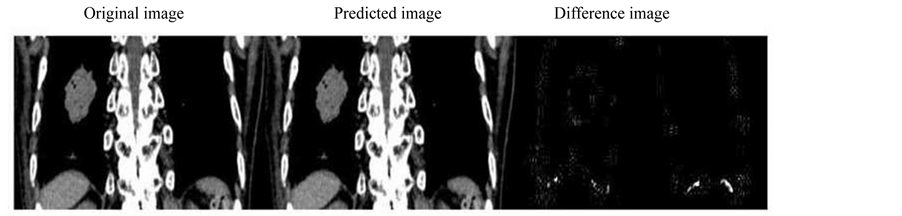

In 4DCT images, a few principal components were enough to represent the original feature of lung motion and deformation; Figure 3 shows the first three principal component images and the representative prediction image is shown in the middle panel of Figure 4 and Figure 5, where only three components were taken into account. One can see that the first principal component represents the entire feature of the body and the other components give a kind of corrections, especially, in the tumor surface and the diaphragm edge. As seen in Figure 4 and Figure 5, the difference from the original image is negligibly small, so that the prediction can be successfully obtained with only first three principal components. The corresponding coefficient values are indicated in Figure 6, where the prediction started after the 42nd step for the next ten steps. The predicted coefficient values are in agreement with the original ones. The evaluated image correlation was 0.9998 ± 0.0001 for large-view 4DCT, and 0.9992 ± 0.0002 for ROI 4DCT (Table 1). Although the value was slightly superior in large-view 4DCT, the calculation time was reasonably reduced in ROI 4DCT (0.6 sec ® 0.12 sec).

Figure 4. Image prediction result for large view 4DCT image which shows the original (left), predicted (center) and the difference image (right).

Figure 5. Image prediction result for ROI, the tumor and its anticipated moving range showing the original (left), predicted (center) and the difference image (right).